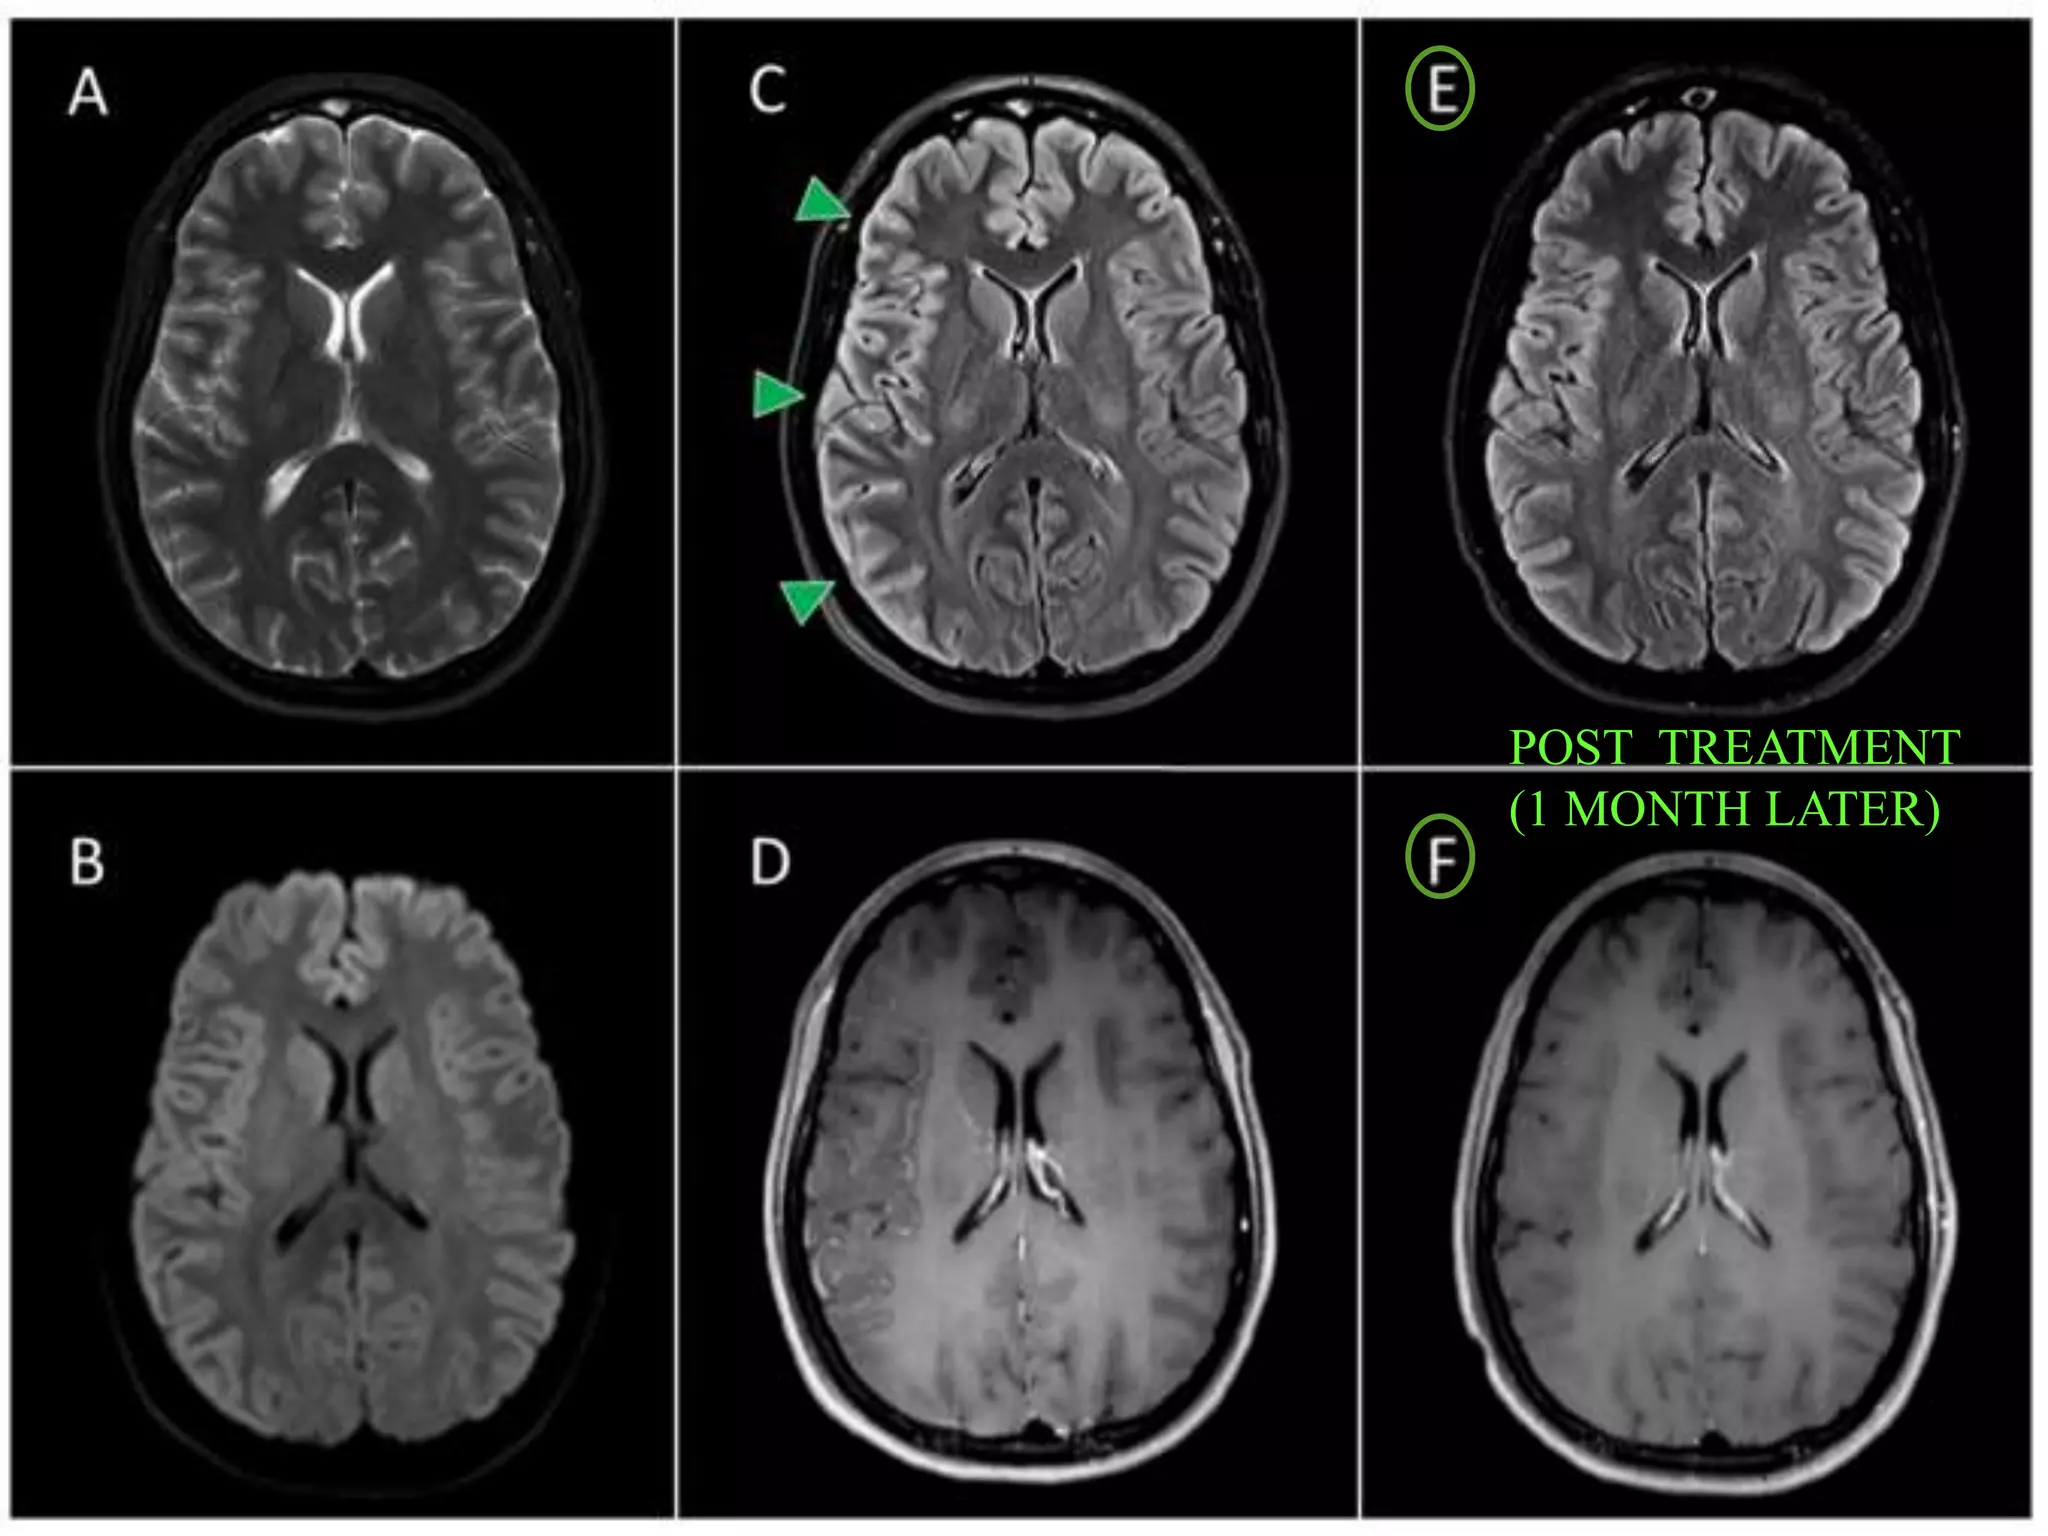

POST TREATMENT

(1 MONTH LATER)